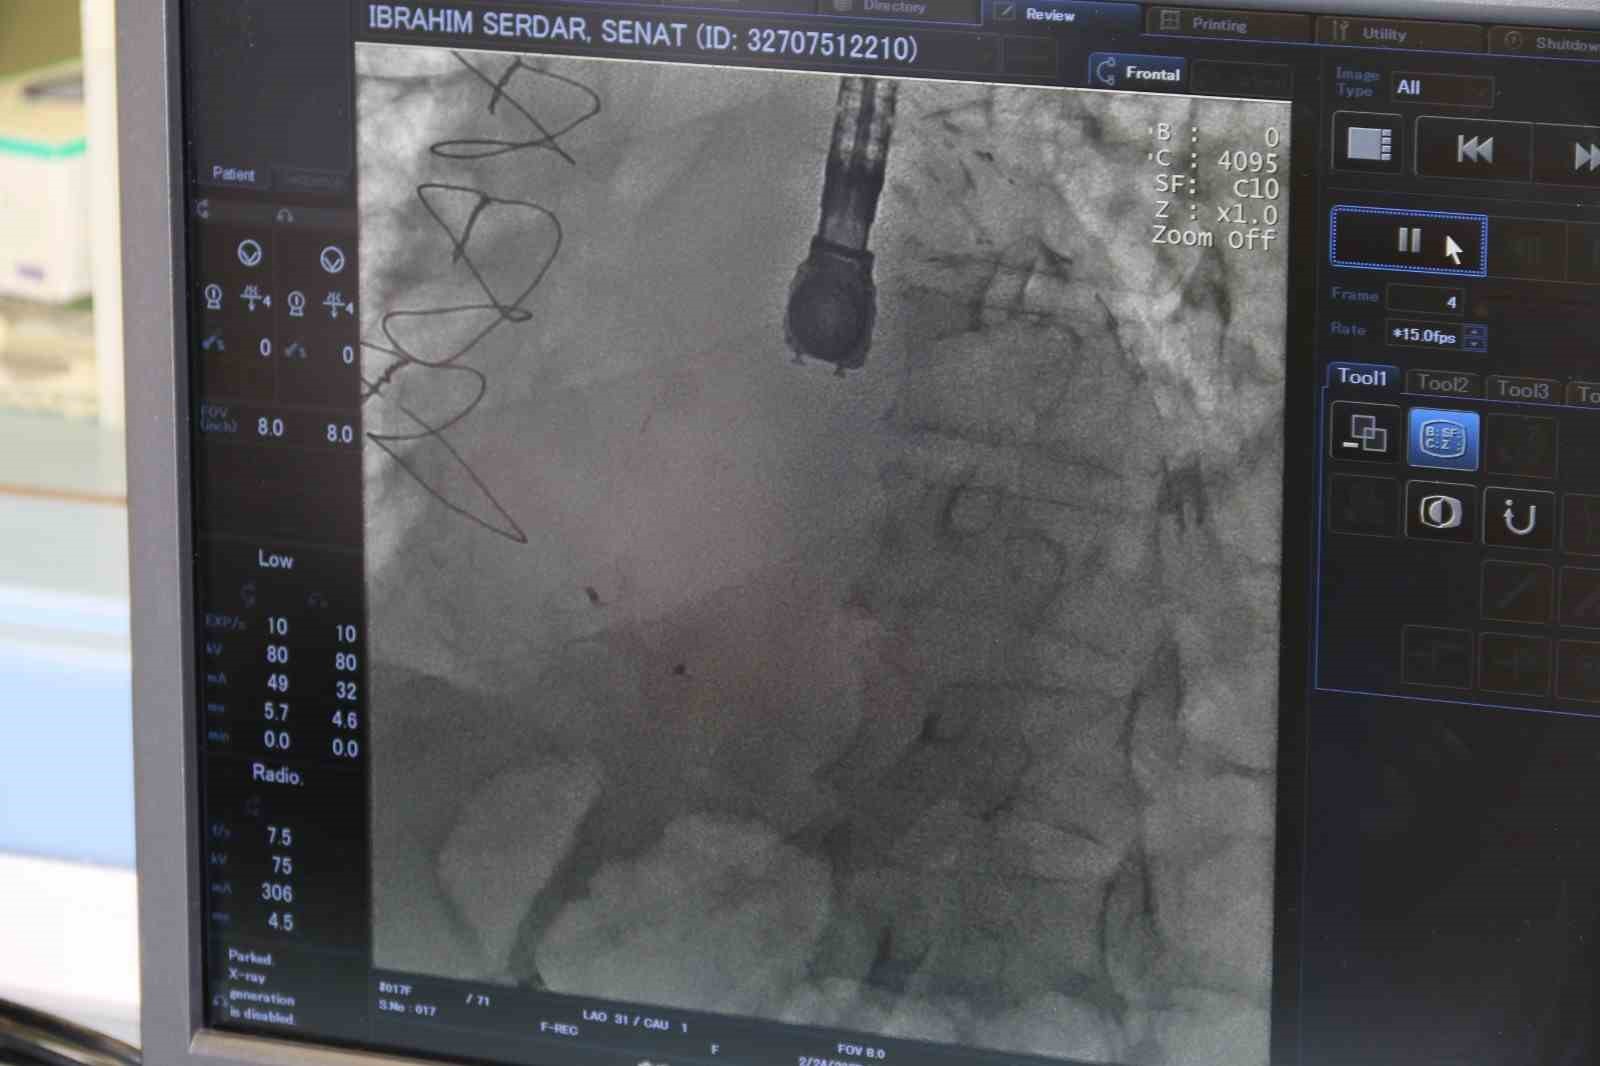

Kardiyoloji Uzmanı Dr. Bektaş Murat, kronik rahatsızlıkları olan ve bunların ameliyatı zorlaştıracağını öngörerek ameliyat kararı aldı. Anjiyografi adlı yöntemle kasıktan girerek kalpteki deliği uzun ve meşakkatli süren ameliyat sonrası kalpteki delik kapatılmış oldu. Ameliyat sonrası durumu takip edilen hasta, taburcu edildi. Böylelikle 68 yaşındaki İbrahim Serdar Şenat, bu operasyonu geçirip de yaşayan 9 hastadan biri oldu.

Operasyonla alakalı konuşan Eskişehir Şehir Hastanesi’nde görevli Kardiyoloji Uzmanı Dr. Bektaş Murat, "Hastamız polikliniğimize nefes darlığı ve kalp yetersizliği semptomuyla başvurdu. Ancak hastamızın hikâyesini aldığımızda yaklaşık 20 gün önce başka bir merkezde kalp krizi geçirdiğini ve anjiyografiyle tedavi edildiğini öğrendik. Muayene sırasında kalp kriziyle beraber ortaya çıkan, kalp karıncıklarının duvarında VSD dediğimiz bir kalp deliğinin meydana geldiğini öğrendik. Bu gerçekten çok ciddi bir durum. Kalp krizine bağlı olarak çok nadir bir şekilde gerçekleşiyor; ancak nadir gelişse de ölümcül olabilen bir hastalık. Dolayısıyla bu gelişen komplikasyonu hızlı bir şekilde tedavi etmemiz gerekiyordu. Onun için hastamızı yoğun bakıma yatırdık ve ileri tetkiklerini yaptık. İleri tetkikler sonucunda ‘Ventriküler Septal Defekt’ (VSD) dediğimiz bu hastalığın, kalp krizine bağlı olarak geliştiğini ve kalbin duvarında delik şeklinde olduğunu tespit ettik. Hastanemizdeki kalp ekibiyle de hemen bir istişare yaparak tedavi yöntemi üzerinde çalıştık. Normalde bu hastalığın tedavisi için ilk aşamada cerrahi müdahale öneriliyor ancak hastamızın altta yatan ciddi hastalıklarının olması nedeniyle cerrahi işlemin çok yüksek riskli olduğu kararına varıldı. Sonrasında bu işlemi girişimsel olarak yapmamız için karar verildi. İlk önce hastamızın acil durumunu tedavi edip sonrasında da ekibimizle beraber kasıktan girme operasyonu yaparak, kalpteki deliği de kapatmış olduk" dedi.